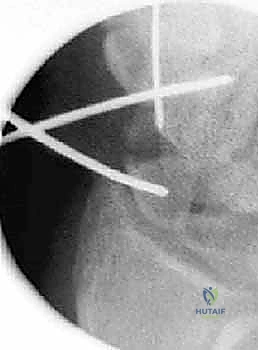

هذه هي التقنية المتقدمة التي يبرع فيها الأستاذ الدكتور محمد هطيف في صنعاء. بدلاً من فتح الرسغ، يتم إجراء العملية بأكملها من خلال شقوق دقيقة لا تتجاوز 2-3 مليمترات، تحت إرشاد جهاز الأشعة المرئية (Fluoroscopy) وبمساعدة المنظار المفصلي الدقيق.

العملية الجراحية بتقنية التدخل المحدود ليست مجرد "إدخال مسمار"، بل هي عمل فني وهندسي دقيق يتطلب مهارة جراحية فائقة، تخطيطاً مسبقاً، وتنسيقاً مثالياً بين يدي الجراح والصور الإشعاعية. يتبع الأستاذ الدكتور محمد هطيف بروتوكولاً صارماً لضمان أعلى معدلات النجاح.